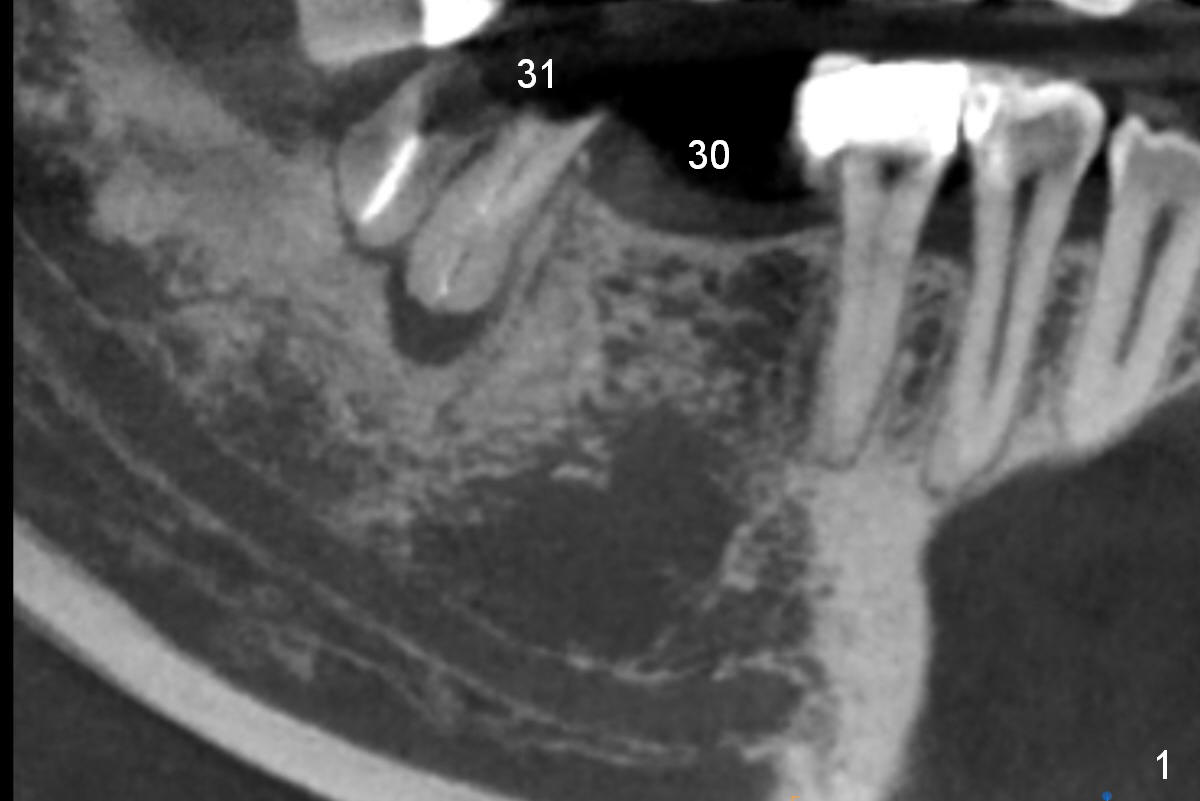

A 47-year-old woman has had 3 bridges. One of them (the lower right) is broken down. The patient requests removing the tooth #31 (Fig.1 CBCT), because of difficulty in keeping it clean. Since the buccal plate is thin (Fig.2 (axial section), 3 (coronal section) >) or absent (Fig.2 *), a 5 mm implant will be placed lingually (Clindamycin).